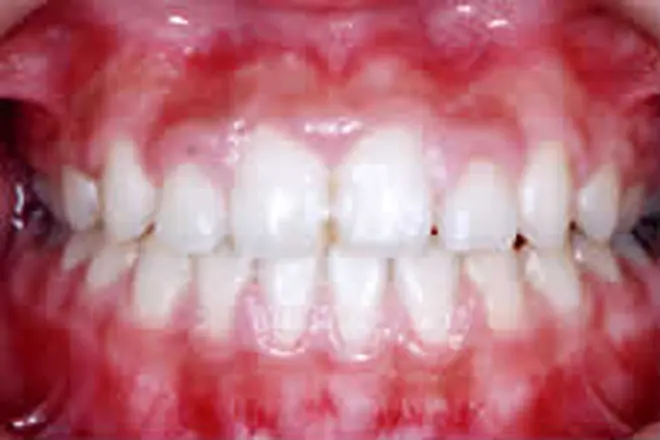

子どもの矯正 治療例1

前歯が出ている状態で反対に噛んでいる場合、自然に治ることはありません。

また、10歳くらいまでは上顎が盛んに成長する時期で、このままだと上顎の成長に支障が出る可能性があります。そこで、前歯の矯正治療を開始しました。

治療期間は6ヵ月で治療完了です。反対咬合が治りました。

この後は数ヵ月に一度、永久歯が生えそろうのを経過観察していきます。

| 患者さまの年齢・性別 | 8歳・女性 |

|---|---|

| 治療期間 | 6ヵ月 |

| 治療費(税込) | 330,000円 |

| 主訴 | 前歯が反対に噛んでいる |

| 診断名・主な症状 | 反対咬合 |

| 治療に用いた主な装置 | 表側矯正装置 |

| 治療内容 |

前歯(永久歯)が萌出した状態で反対に咬んでいる場合、自然に治ることはありません。また10歳くらいまでは上顎の骨が盛んに成長する時期であり、この状態では上顎の成長が充分に得られない可能性があるため、早めの治療が必要になります。 |

| 抜歯部位 | 非抜歯 |